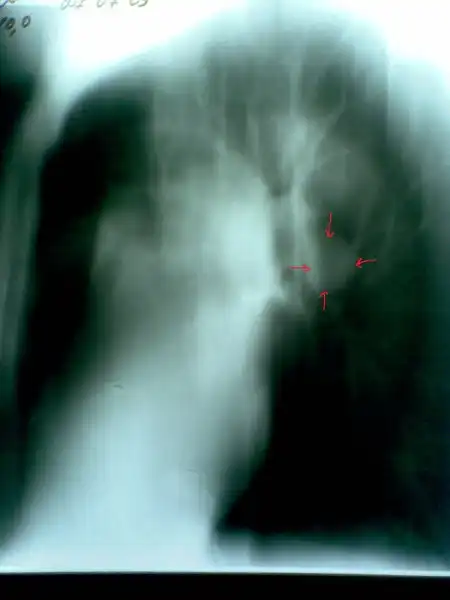

Рак легких в рентгеновском изображении

Пациент № 3:

Пациент № 4:

Пациент № 6:

Пациент № 7:

2. По поводу снимков... Сомнение вызывает первый пациент. 2 фокуса в разных легких... Разве что метастазы в прикорневые л\у правого легкого... Да и контуры очень четкие в левом легком... Верхняя доля... Дорожка к корню... Больше похоже на туберкулез ИМХО. Хотя и лучистость есть... Спорно.

Пациенты 6 и 7 тоже под вопросом... Не четкая картина.